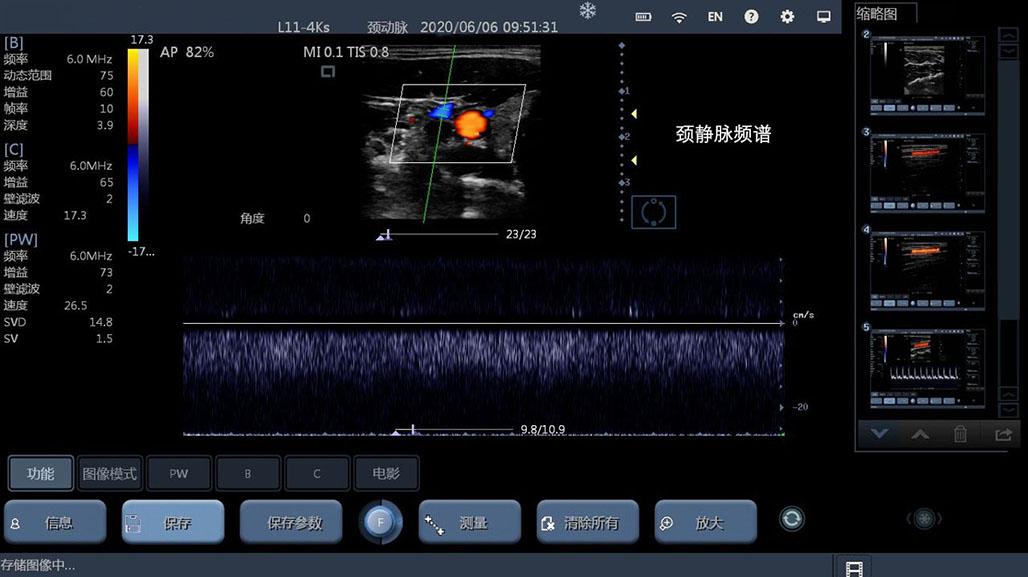

• 线阵

血管